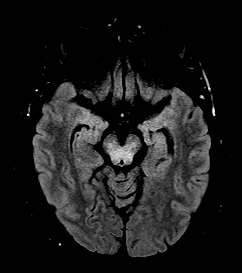

Results: A 38-year-old male developed tremors affecting the head and bilateral upper extremities two weeks after initiating escitalopram for anxiety. Head tremor had oscillations in vertical and horizontal planes. Upper extremities had Holmes tremor[4]–[6], 3–5 Hz in frequency, low-amplitude, seen at rest and action. Tremors persisted despite discontinuation of escitalopram. Magnetic Resonance Imaging showed extensive patchy, confluent T2 FLAIR signal abnormality involving bilateral basal ganglia, midbrain, and bilateral medial temporal lobes with punctate foci extending superiorly into the corona radiata, without gadolinium enhancement. This was stable on serial imaging. Cerebrospinal fluid (CSF) analysis showed oligoclonal bands and lymphocytic pleocytosis. Infectious, autoimmune, and paraneoplastic panels (serum and CSF) were negative except for minimally elevated Glutamic Acid Decarboxylase (GAD-65) antibodies in serum only. A PET scan identified increased uptake in left thyroid lobe, and histopathology from thyroidectomy confirmed papillary thyroid carcinoma. With imaging and serological workup suggesting paraneoplastic/autoimmune rhombencephalitis, immunotherapy with pulse steroids and plasma exchange was initiated without significant benefit. Intravenous immunoglobulin and cyclophosphamide provided limited neurological improvement. Tremors were refractory to multiple medication trials: head tremor responded to botulinum toxin injections, and trihexyphenidyl modestly improved upper extremity tremors. Over the next two years, he developed pseudobulbar affect and progressive gait instability, leading to walker-dependence.

Midbrain and Bitemporal T2/FLAIR Hyperintensities